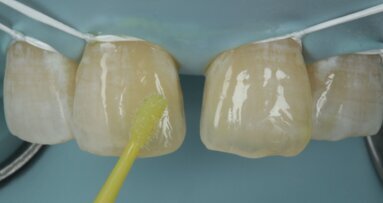

Desaturation was achieved by layering a deeper darker dentin [ A3 Dentin - Fig 12 ] inside and a lighter dentin [ A2 Dentin - Fig 13 ] shade over it in the shape of three mamelons. Incisal Halo was achieved by layering an Achromatic Enamel [clear translucent] shade around the mamelons [ Fig 14 ] and the A2 dentin shade on the incisal edge [ Fig 11 ]. Final layer of A2 Enamel shade was used covering the restoration in 0.5mm thickness so as to avoid too much translucency [ Fig 15 ]. Finishing and polishing were done using the 3M Soflex discs and spirals [ Fig 17 ] as recommended by the manufacturer.

Fig 12 Dark dentin shade layered

Fig 13 light dentin shade placed above dark dentin

Fig 14 translucent shade placed in between mamelons